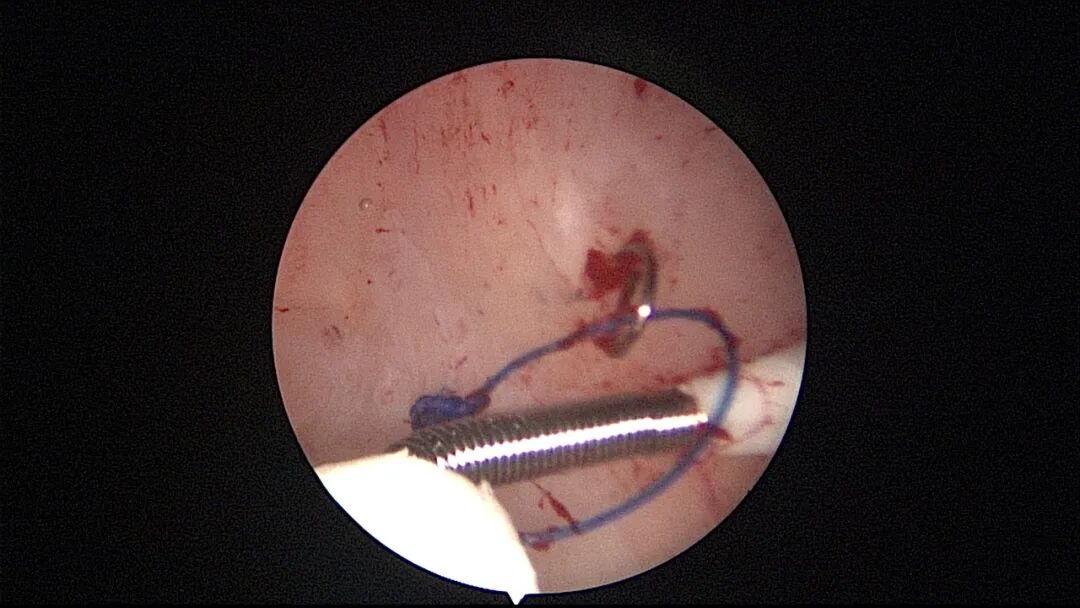

操作步骤描述:宫腔检查镜可完成操作,扩张宫颈至7号扩宫棒,检查镜能轻松通过,避免镜鞘与节育环纵臂在宫颈管形成卡压及筷子效应,影响操作,或卡压摩擦阻力大带出节育环。可用单级电针在宫底扎出小凹坑做标记或作为置入挂钩的隧道(不是必须的)。将挂钩用异物钳直视下送入宫腔,或用中弯钳盲视下送入宫腔,异物钳夹持挂钩将倒钩端插入宫底肌层,越过倒钩。用环尾丝或不可吸收线在节育环顶端打结,形成一个线圈,直径约0.5cm~1cm,结打在线圈旁边,便于夹持操作。将环装回推杆送入宫腔,再夹住节育环固定线圈抵紧宫壁稍旋转就可以将线圈滑进挂钩缺口,挂到挂钩上,可再次向宫底推送挂钩少许,不必夹闭挂钩缺口,重力作用和内膜生长都会阻止线圈脱出,可以用电针电凝挂钩周围组织,进一步防止挂钩脱落。异物钳原位固定节育环,退出宫腔镜,距宫颈外口0.5cm~1cm剪断剩余尾丝。宫颈扩张到9号扩宫棒,冷刀系统异物钳夹持挂钩及线圈也可完成以上操作。

取胚术后丝线挂钩固定节育环图片及视频

子宫腺肌症内膜息肉切除后丝线挂钩固定曼月乐并电凝图片及视频

异常子宫出血内膜增生节育环尾丝挂钩固定曼月乐图片及视频